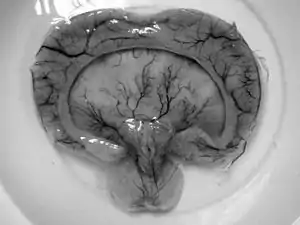

- Alobar holoprosencephaly, the most serious form, in which the brain fails to separate, is usually associated with severe facial anomalies, including lack of a nose and the eyes merged to a single median structure (see cyclopia).

- Semilobar holoprosencephaly, in which the brain's hemispheres have somewhat divided, is an intermediate form of the disease.

- Lobar holoprosencephaly, in which there is considerable evidence of separate brain hemispheres, is the least severe form. In some cases of lobar holoprosencephaly, the patient's brain may be nearly normal.

- Syntelencephaly, or middle interhemispheric variant of holoprosencephaly (MIHV), in which the posterior frontal lobe and the parietal lobe are not properly separated, but the rostro basal forebrain properly separates; it is possible that this is not a variant of HPE at all, but it is currently classified as such.[2]